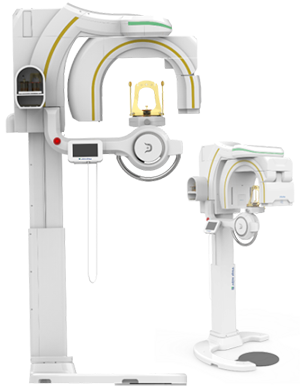

Dentri Max CBCT - from HDX Will (16x18) - Call for Special Pricing

Introducing the Dentri Max, a game-changer in dental imaging tailored just for you! With its impressive Field of View (FOV) of 18 x 16.5cm, this model promises visually stunning images that redefine precision diagnostics.

Designed to cover a wide spectrum of dental needs, the Dentri Max is your all-in-one solution for endodontics, implantology, craniomaxillofacial, and cephalometric analysis. Say goodbye to blurry images and hello to crystal-clear clarity, thanks to its cutting-edge image-processing algorithm and metal artifact reduction technology.

Cephalometric X-ray (optional)

Optional cephalometric arm, excellent for orthodontic practice